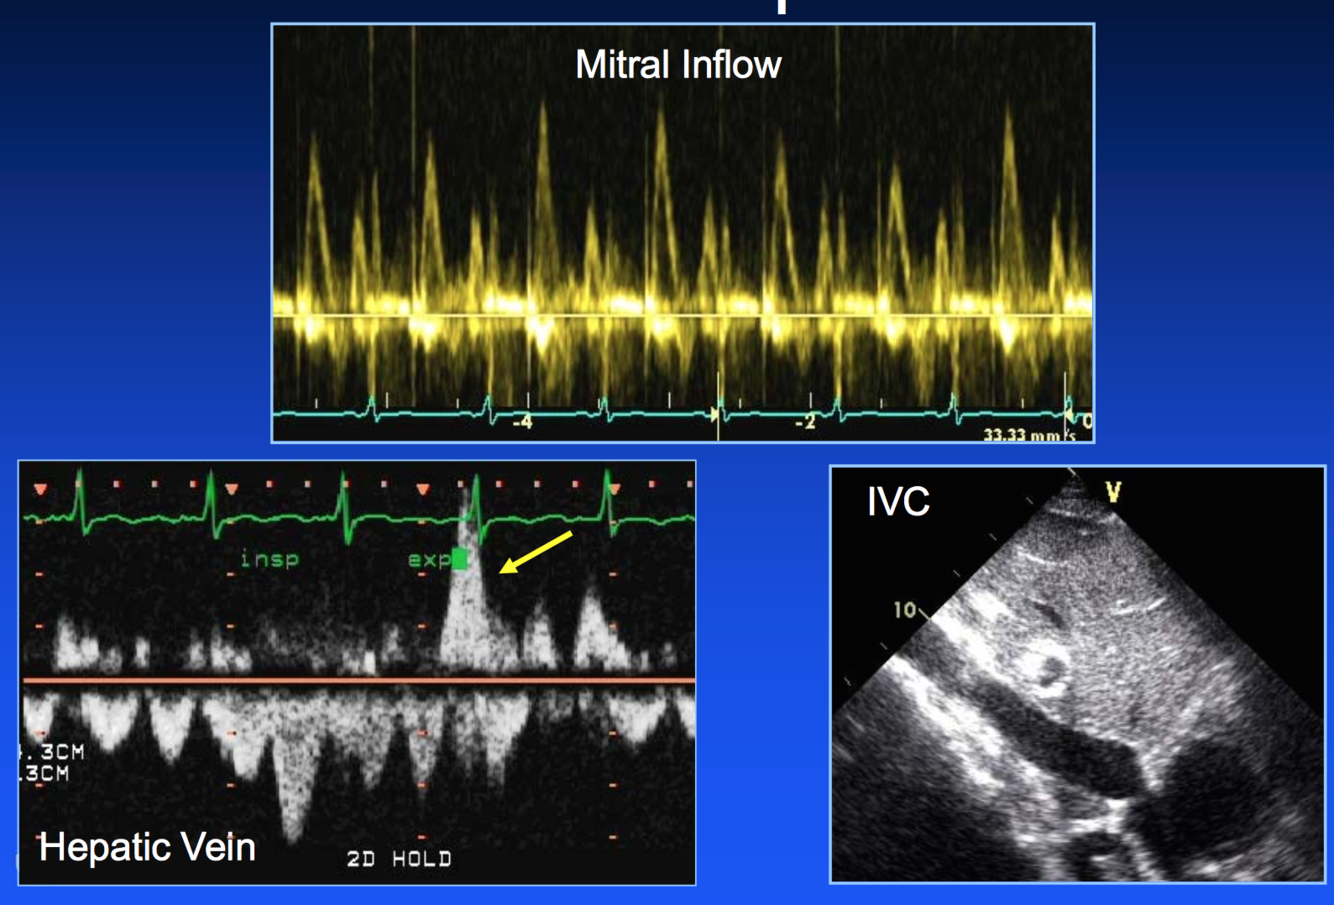

Dx?

tamponade (note PE, subtle septal shift to RV on inspiration)

tamponade (mitral inflow resp variation, HV dias flow rev, IVC plethora)